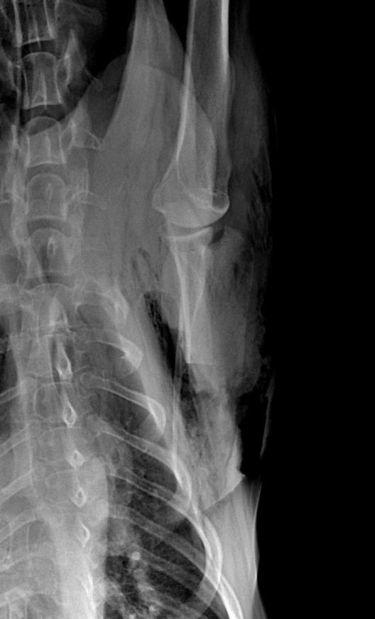

Au niveau du thorax, en revanche, une très volumineuse masse est présente dans le poumon droit dont le volume est supérieur à celui du cœur (12×9 cm sur la vue de face) ainsi que de plus petites masses métastatiques (fig. 12 et 13). Les propriétaires refusent d’aller plus loin dans les examens (scanner/biopsies…).

Plusieurs masses tumorales sont présentes dans le poumon droit dont la plus grosse a un diamètre de 12*9 cm sur la vue de face.